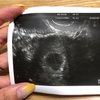

第二子② 【BT12】判定日

今日は待ちに待った判定日。

HCG 584.5!

よかった!とりあえず第一関門は突破!